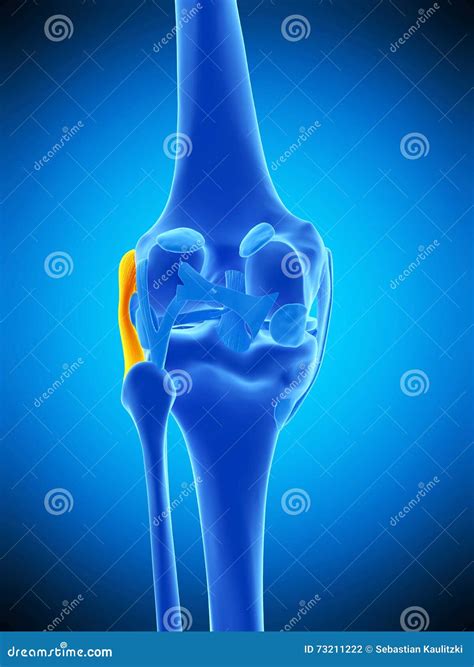

The Fibular Collateral Ligament, frequently referred to by medical professionals as the Lateral Collateral Ligament (LCL), is a critical component of the knee joint's stability. Located on the outer side of the knee, this band of fibrous connective tissue connects the femur (thigh bone) to the fibula (the smaller bone in the lower leg). While often overshadowed in popular culture by the more commonly injured Anterior Cruciate Ligament (ACL), the Fibular Collateral Ligament is essential for maintaining proper knee alignment and preventing excessive side-to-side movement, particularly when the leg is subjected to force from the inside.

Understanding the anatomy of the Fibular Collateral Ligament is crucial for grasping how it protects the knee. Unlike the Medial Collateral Ligament (MCL), which is attached to the joint capsule and the meniscus, the LCL is a distinct, cord-like structure that sits entirely outside the joint capsule. This anatomical positioning grants it a different injury profile compared to other knee ligaments.